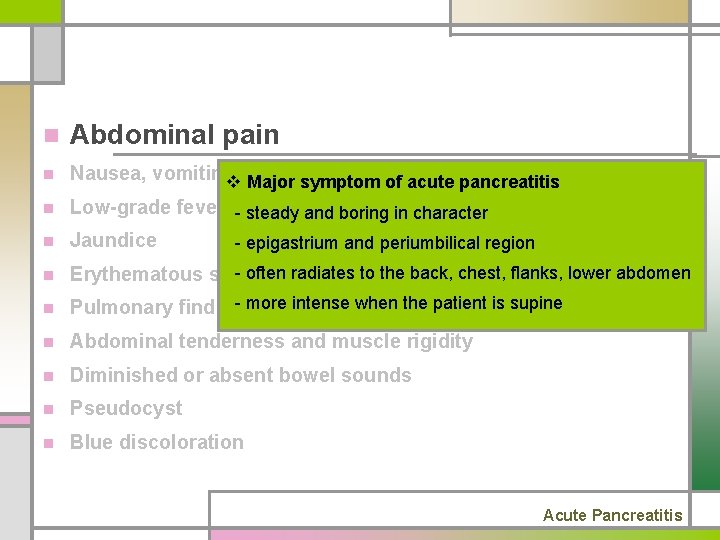

n Abdominal pain n Nausea, vomiting, abdominal distention n Low-grade fever, tachycardia, hypotension, shock n Jaundice n Erythematous skin nodules n Pulmonary findings (atelectasis, pleural effusion) n Abdominal tenderness and muscle rigidity n Diminished or absent bowel sounds n Pseudocyst n Blue discoloration Acute Pancreatitis

n Abdominal pain n Nausea, vomiting, distention v abdominal Major symptom of acute pancreatitis n Low-grade fever, -tachycardia, hypotension, steady and boring in charactershock n Jaundice n - often radiates to the back, chest, flanks, lower abdomen Erythematous skin nodules n - more intense whenatelectasis, the patient is pleural supine effusion) Pulmonary findings (basilar rales, n Abdominal tenderness and muscle rigidity n Diminished or absent bowel sounds n Pseudocyst n Blue discoloration - epigastrium and periumbilical region Acute Pancreatitis